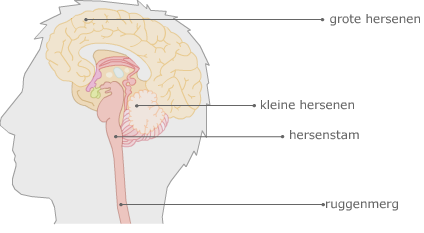

Grote hersenen

Grote hersenen:

De grote hersenen zijn onderdeel van het

centraal zenuwstelsel. De grote hersenen verwerken impulsen afkomstig van zintuigen. De grote hersenen zijn ook de plek waar logisch redeneren, planning, geheugen en emotie plaatsvinden.

Kleine hersenen:

Zorgen voor de fijne afstelling tussen waarnemingen en bewegingen. De kleine hersenen controleren houding en evenwicht. Alles wat je nieuw leert, wordt (waarschijnlijk) opgeslagen in de kleine hersenen.

Hersenstam:

Ligt in het verlengde van het ruggenmerg. De hersenstam is het oudste hersendeel en bestaat uit korte zenuwcellen. De hersenstam regelt belangrijke basisfuncties om te overleven, zoals de bloedsomloop, slaap-waakritme, ademhaling en regeling van de spijsvertering.

Ruggenmerg:

Het ruggenmerg is onderdeel van het

centraal zenuwstelsel. Het ruggenmerg kan impulsen afkomstig van pijnzintuigen verwerken. Het resultaat is een

reflex.